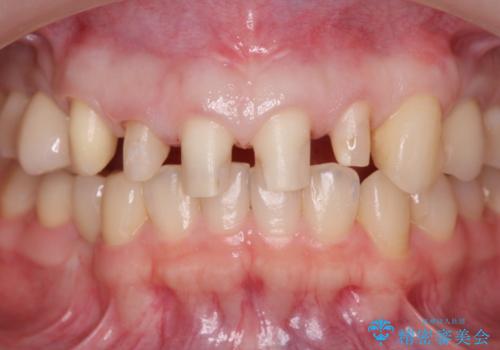

多発した前歯の重度虫歯治療

- 放置した虫歯の歯がボロボロになってしまい治療を希望され来院されました。

残根状態の歯、神経まで虫歯が達し失活した歯、歯肉縁下まで及んだ虫歯が多数認められます。